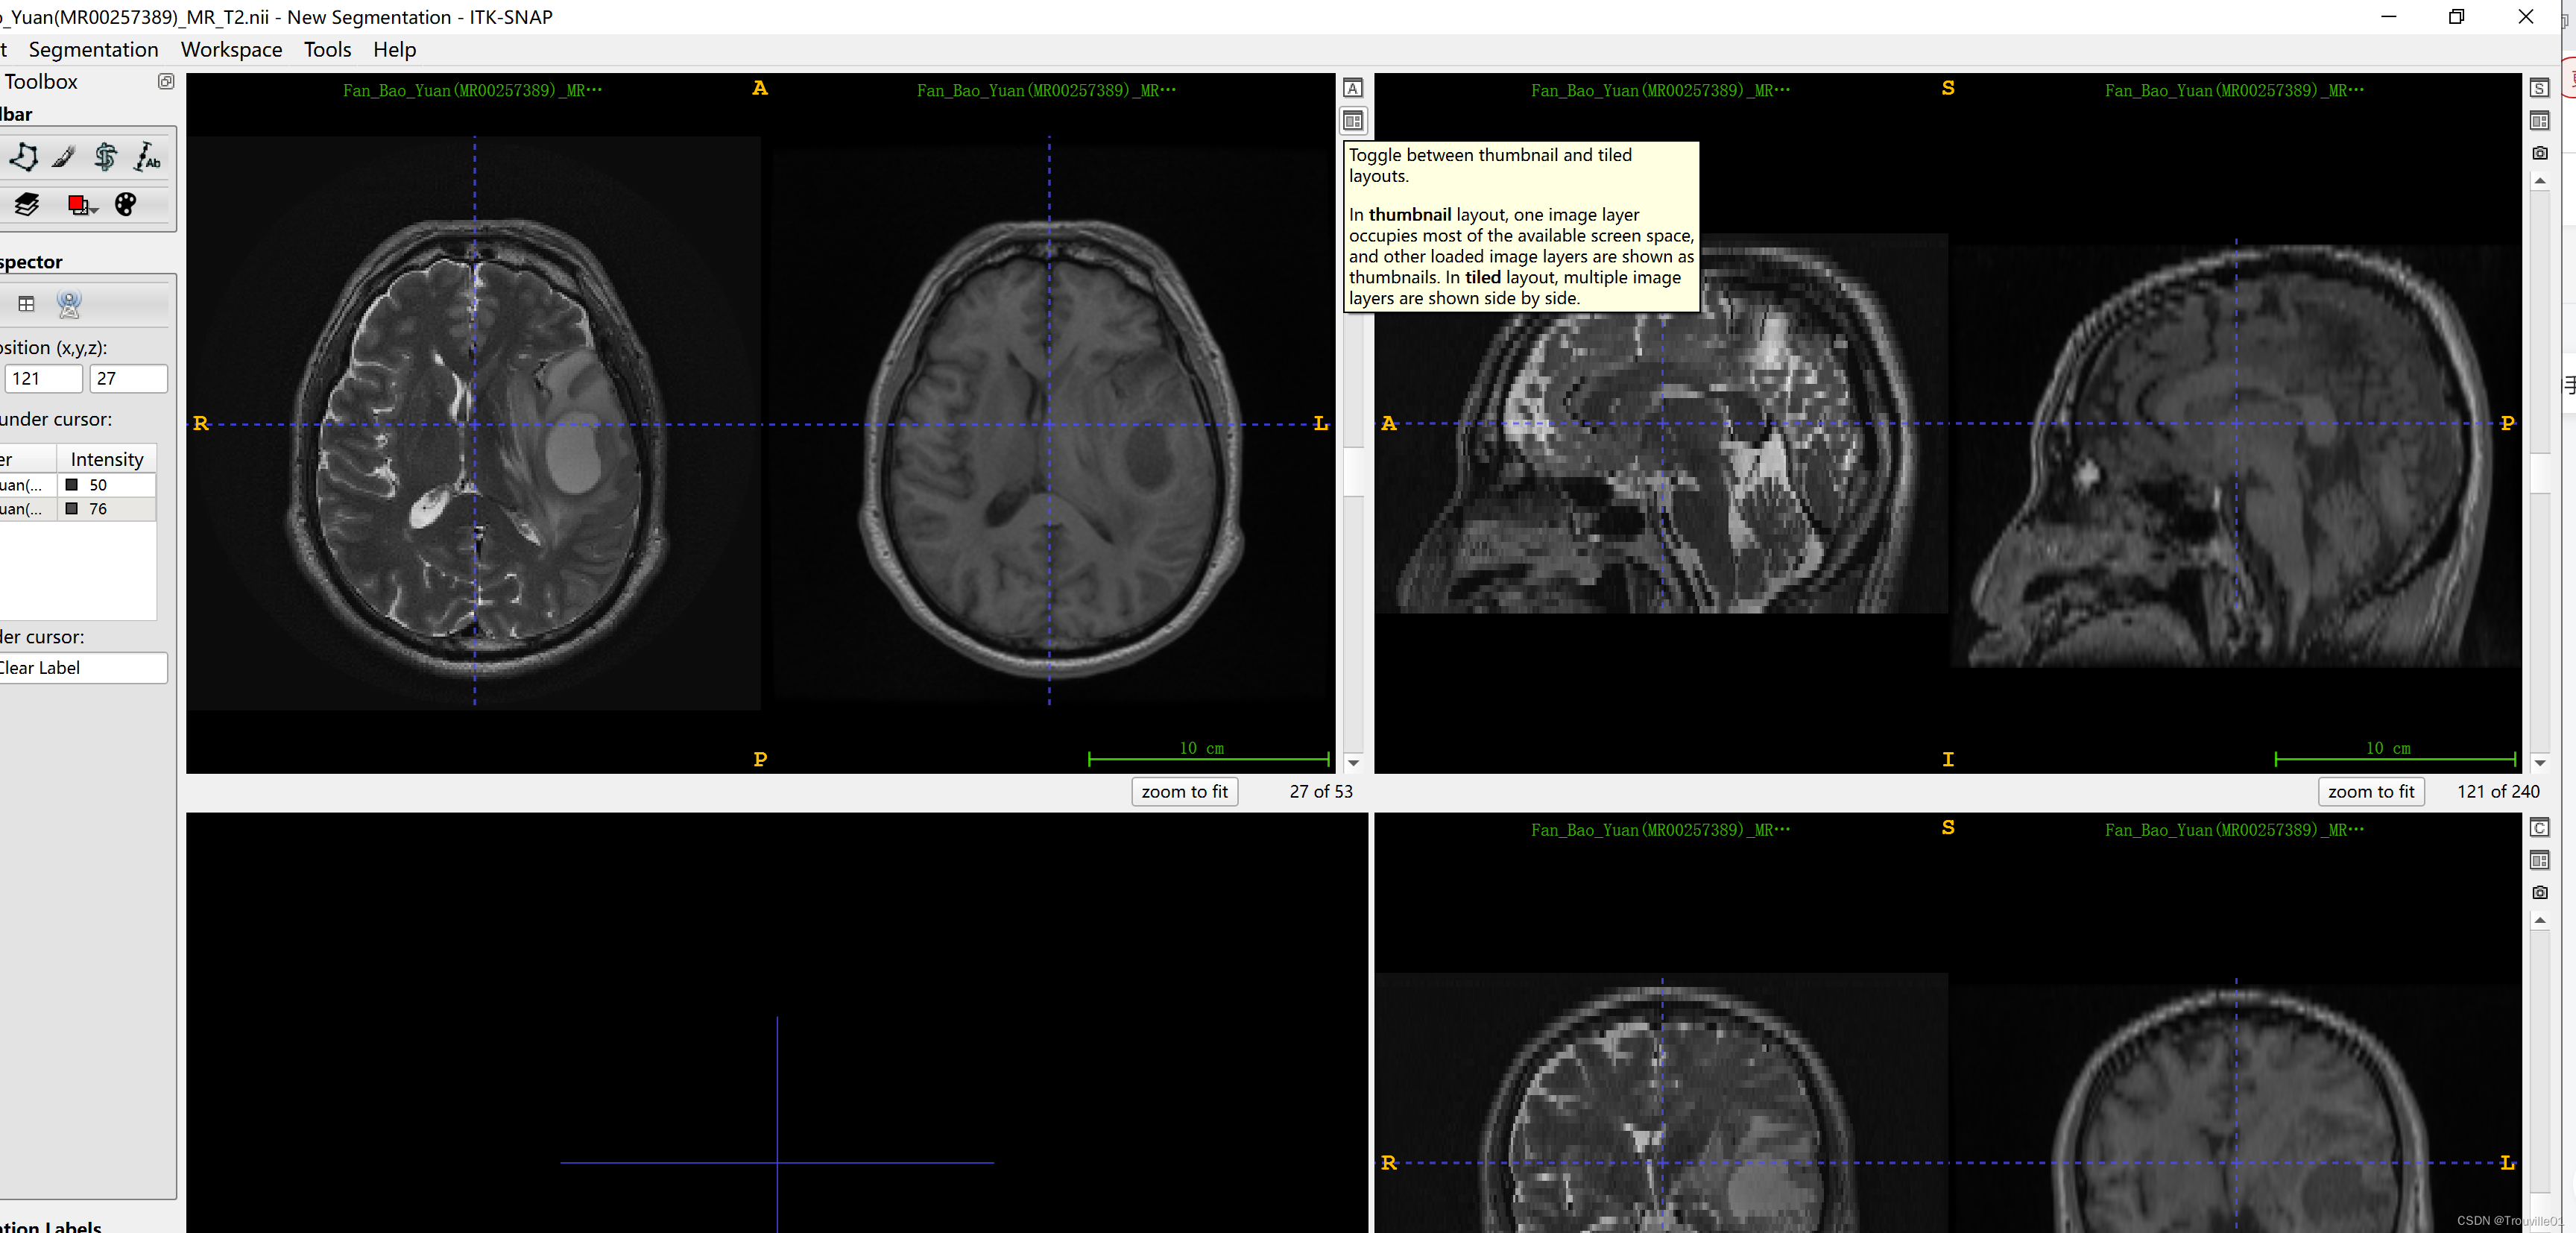

3.单击小控件(显示提示的那个控件),改变排列方式